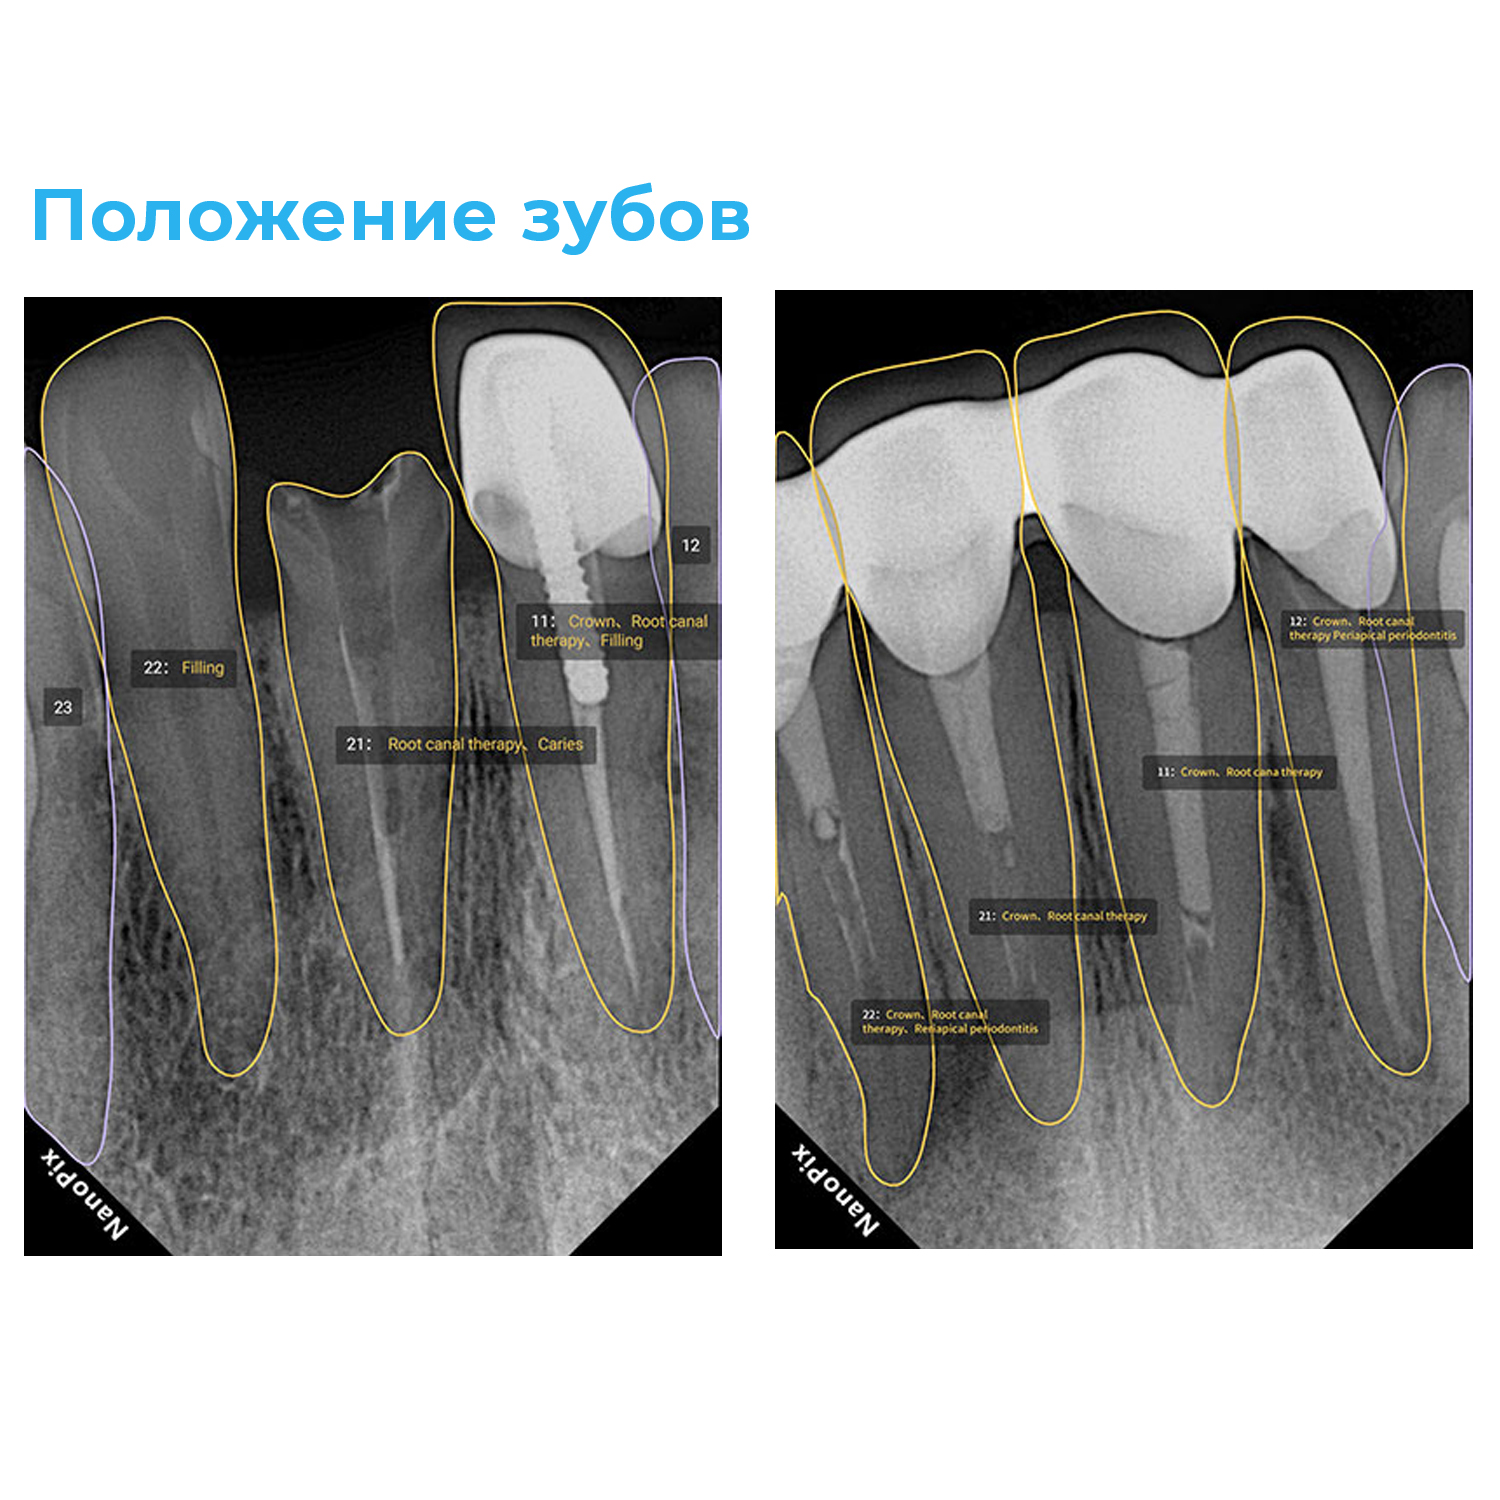

Прибор оснащён высокочувствительным сенсором, с помощью которого устройство фиксирует и передаёт изображение в цифровом виде на компьютер. Принцип работы заключается в следующем: цифровой радиовизиограф размещается в ротовой полости пациента за зубами. С щёчной стороны дентальный рентгеновский аппарат выпускает в направлении радиовизиографа рентгеновские лучи. Лучи, проходя через ткани зуба, фиксируются на радиовизиографе, и полученная информация отображается на экране компьютера. Уникальная технология искусственного интеллекта Nano AI распознаёт зубные патологии, выделяя их цветом и предлагая возможные способы лечения.